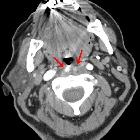

Ectopic

internal carotid artery presenting as an oropharyngeal mass. a. CT scan of the neck, following contrast administration. Axial section of the level of the oropharynx, demonstrates the horizontal extension of the right ICA towards the midline and behind the oropharynx. b. Multiplanar reconstruction at the coronal plane demonstrates an angiographic appearance of the vessels of the neck, showing the ectopic portion of the right ICA.